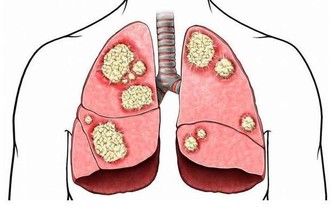

「意念轉圈」不僅可以治療失眠,還能幫我們消除高血壓、心臟病的隱患,而且抑鬱、焦慮、煩悶等不良情緒也會跟著消失。